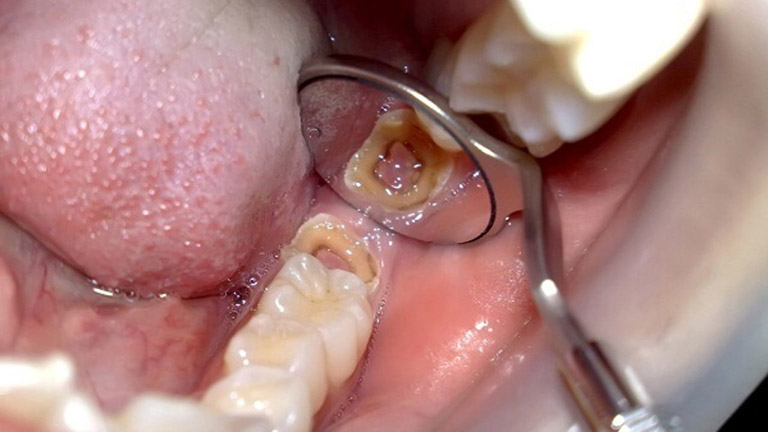

2.3 Răng khôn mọc đúng vị trí, thẳng nhưng hình dáng dị dạng

Răng khôn mọc đúng vị trí, thẳng hàng nhưng lại có một số điểm khác thương: nhỏ, dị dạng,.. Từ đó tạo thành địa điểm giắt thức ăn, tạo điều kiện thuận lợi cho vi khuẩn phát triển, gây sâu răng, viêm nha chu và các bệnh lý răng miệng khác.